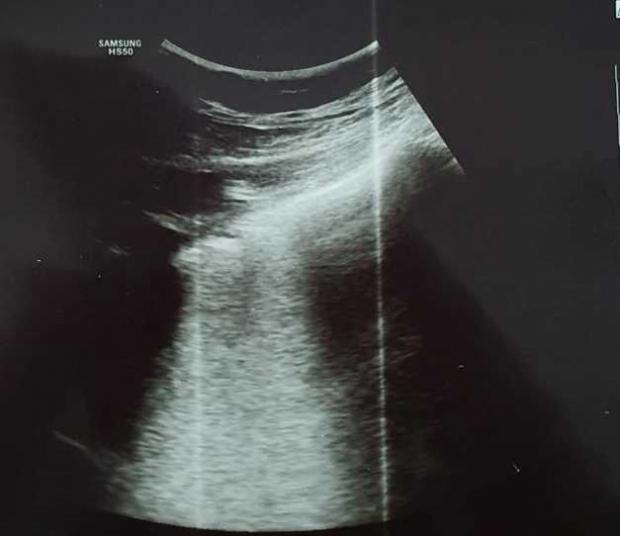

"Imagine de ecografie pulmonară cu o bandă albă în spatele pleurei -Linii B confluente- sugestivă pentru inflamaţia alveolo-interstiţială", a scris medicul.